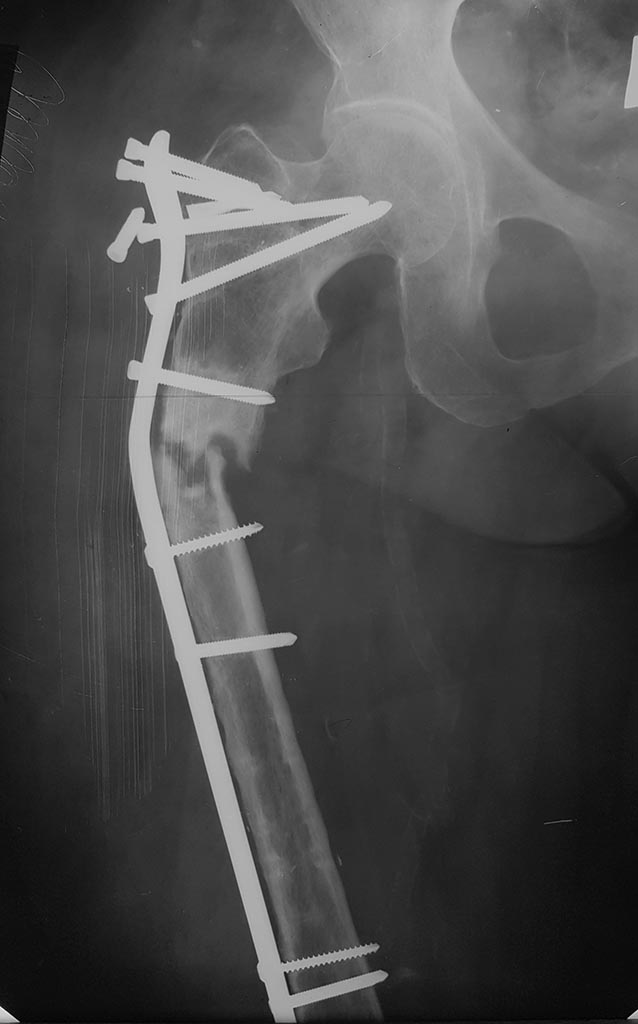

[Ortho] Атрофический псевдоартроз бедра

Пациентке 70 лет. В 2015 году - перелом верхней трети бедра, МОС

пластиной. Через 2 года удаление пластины, через несколько дней -

спонтанный перелом в том же месте. Выполнен реостеоситез с костной

аутопластикой.  В течение 3 мес  после реостеосинтеза - субфебриллитет.

Травматолог в поликлинике разрешил  осевую нагрузку через 3 недели после

МОС. На сегодняшний день прошло  8 месяцев  после реостеостеосинтеза.

СОЕ - 30,  С-реакт белок 12, сдвига в формуле нет, свободной жидкости в

зоне  несращения нет. Думаем удалить пластину и  винты,  резецировать

зону  псевдоартроза ( уйдет 4- 6 см),  фиксировать